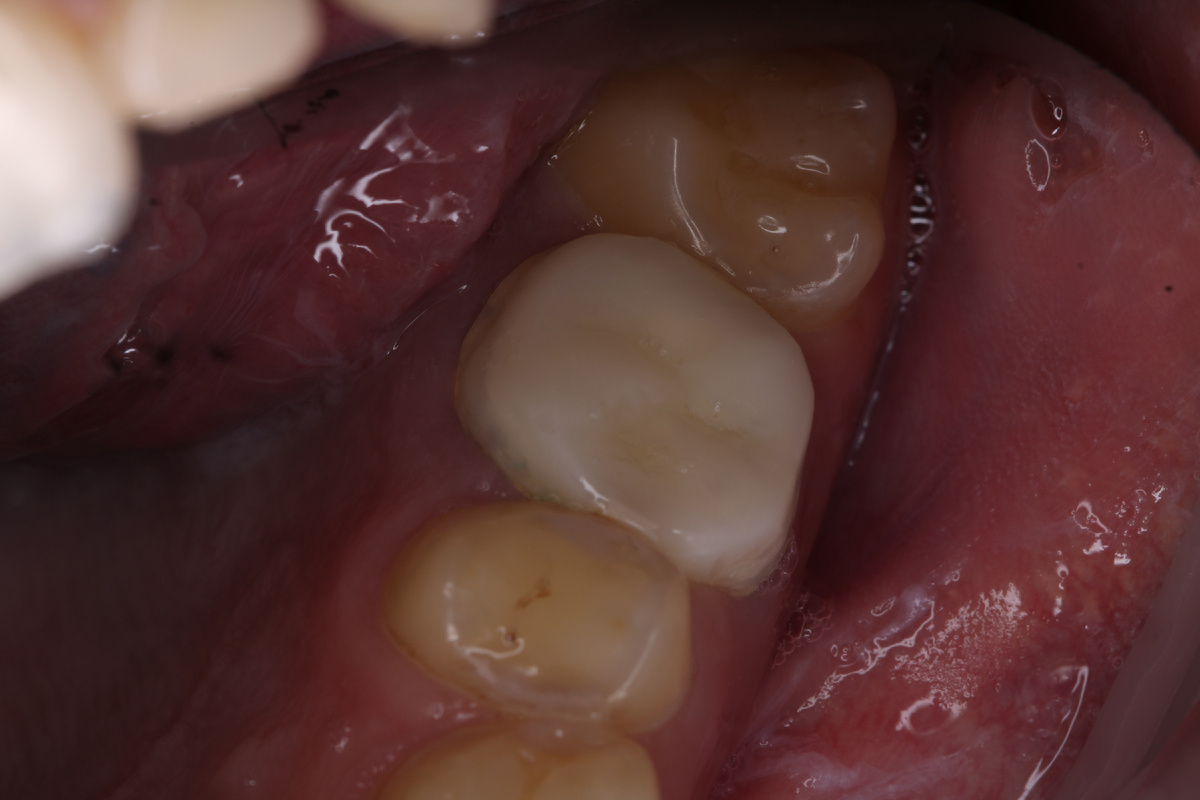

Искусственная коронка из диоксида циркония зафиксирована на постоянный цемент.

Плотное прилегание к десне со всех сторон.